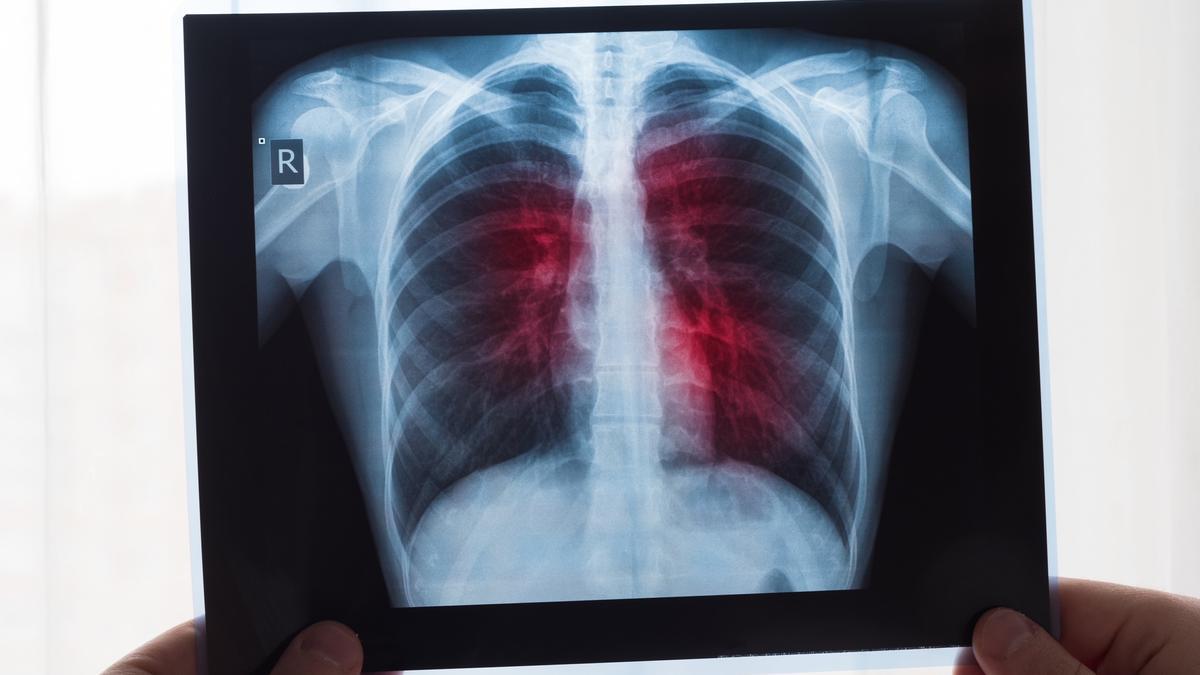

Radiografía de unos pulmones

Radiografía de unos pulmones / EP